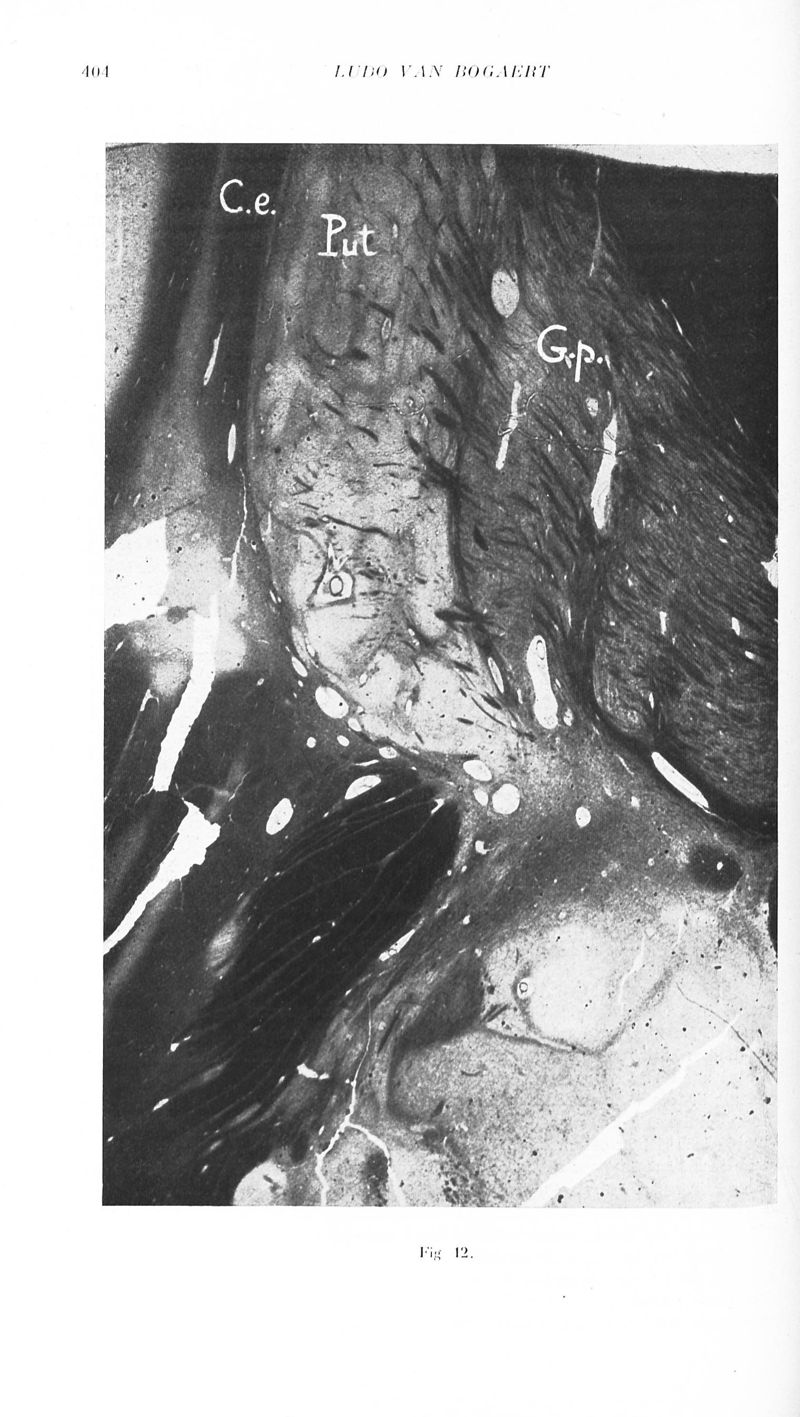

Revue neurologique

1929, vol 2. - Paris : Masson , 1929.